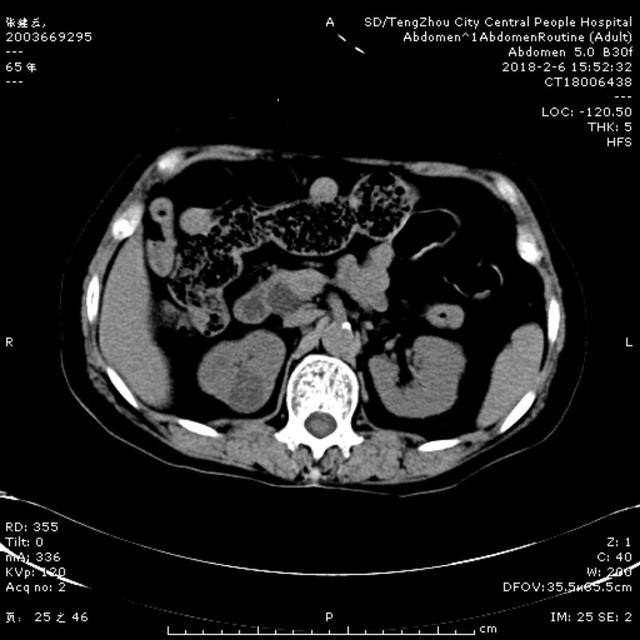

2月6日15:00,一65歲女性患者,因腹痛5天,伴寒戰,發熱,惡心,嘔吐,在當地診所治療,效果差,以“腹痛待查”收住消化內二科。入院查體:體溫37.1℃ 血壓140/90mmHg,急性病容,鞏膜輕度黃染,心肺未及異常,腹部平坦,右上腹壓痛伴反跳痛,肝區叩擊痛陽性,雙下肢無水腫。入院后給予抗炎、補液處理。急查肝功示谷丙轉氨酶561U/L, 谷草轉氨酶798U/L, 總膽紅素64.9umol/L ,直接膽紅素58.9umol/L,血常規示白細胞5.44X10^9/L, 中性粒細胞4.69X10^9/L,凝血常規示正常,行腹部CT可見膽囊壁增厚,膽總管擴張,考慮膽系感染、 膽總管結石可能性大。